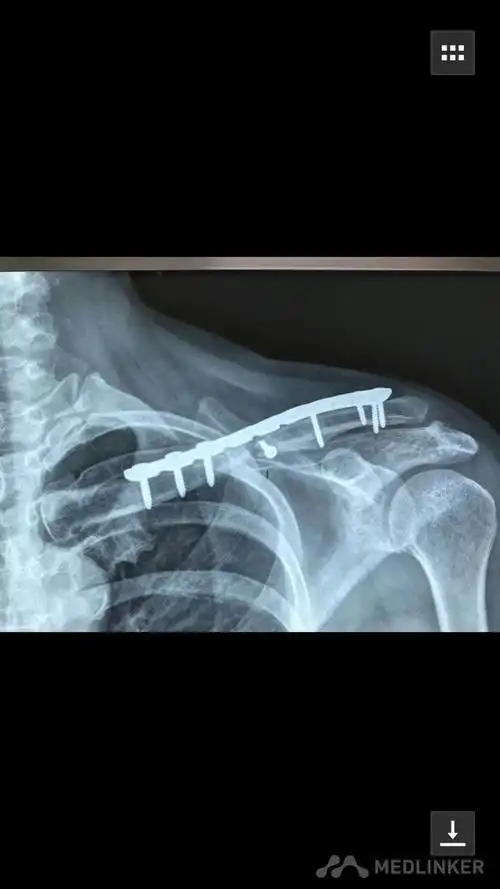

锁骨骨折

肩锁关节脱位锁骨远端骨折关节镜下微型钢板固定喙锁 斜方韧带重建术